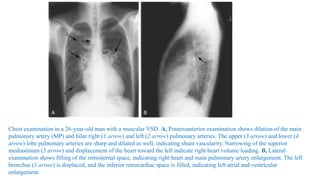

Chest examination in a 26-year-old man with a muscular VSD. A, Posteroanterior examination shows dilation of the main

pulmonary artery (MP) and hilar right (1 arrow) and left (2 arrow) pulmonary arteries. The upper (3 arrow) and lower (4

arrow) lobe pulmonary arteries are sharp and dilated as well, indicating shunt vascularity. Narrowing of the superior

mediastinum (5 arrow) and displacement of the heart toward the left indicate right heart volume loading. B, Lateral

examination shows filling of the retrosternal space, indicating right heart and main pulmonary artery enlargement. The left

bronchus (1 arrow) is displaced, and the inferior retrocardiac space is filled, indicating left atrial and ventricular

enlargement.